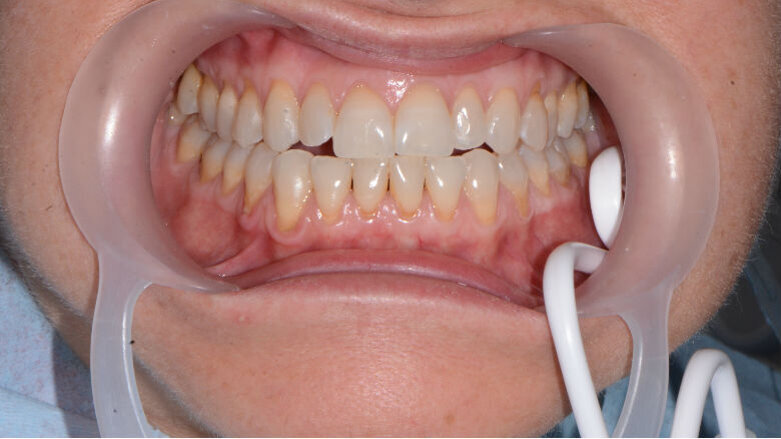

La scelta di una seduta o sgabello non ergonomica diventa una scelta importante, considerando il timing frequente di utilizzo. Usare i divaricatori durante l’esecuzione odontoiatrica (Fig. 3), eviterà il disagio dell’affaticamento all’assistente odontoiatrica poiché eliminerà le tensioni alle articolazioni della mano durante il divaricamento con specchietto, con l’obbiettivo di facilitare la visuale dell’operatore assistito. L’utilizzo degli ingranditori ad esempio (Fig. 4), aiutano l’operatore a mantenere una giusta postura alla poltrona odontoiatrica e migliorano la visibilità del sito clinico, diminuendo i tempi di lavoro e soprattutto migliorando l’efficacia della prestazione. Un rivelatore di placca potrà permettere di visualizzare la topografia del biofilm batterico per permettere un deplaquing efficace (Fig. 5), che non sprechi polvere di glicina o di bicarbonato, contenendo il timing dell’operatività di airpolishing e limitando l’inquinamento dell’ambiente. A livello internazionale esiste un brand che lavora su strumenti ideati da addetti al settore che risultano essere altamente ergonomici poiché basati sull’esperienza della pratica clinica di professionisti.